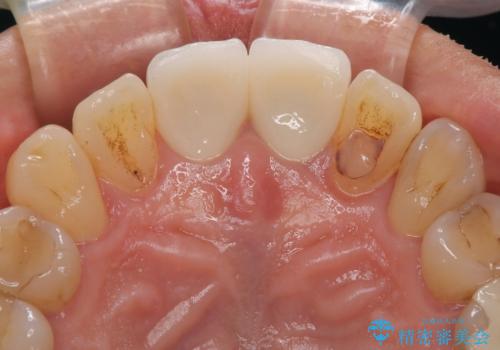

左右対称の2本の歯にセラミッククラウンを装着したことで、調和の取れた審美的な口元となりました。